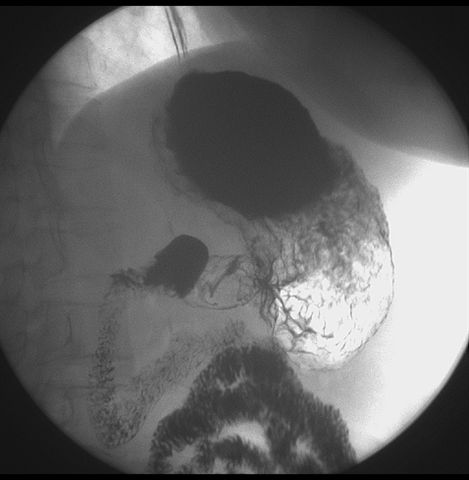

标题: X6872:F,69y,胃部不适。

胃窦至幽门段胃壁僵硬,扩张受限,局部纠集粘破坏,呈杵状。提示溃疡癌变可能性大。

支持考虑胃窦癌可能,胃内滞留液太多,胃窦部僵硬。

胃窦部见钡池影,局部粘膜紊乱,纠集呈杵状改变,胃壁扩张受限,胃窦癌可能性大,建议胃镜检查.

胃窦占位。大量滞留液?十二指肠球炎?

胃窦部管腔扩张度较差,形态略有改变,胃窦粘膜显示欠佳,胃窦部占位可能性大,结合胃镜活检。

北京肿瘤医院胃镜诊断皮革胃。